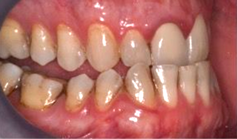

Fig 8. A class III adult male patient required surgical orthodontic treatment. The patient had anterior and posterior crossbites and required leveling of a deep curve of Spee during presurgical orthodontics.

Figure 8

Fig 9. A class III adult male patient required surgical orthodontic treatment. The patient had anterior and posterior crossbites and required leveling of a deep curve of Spee during presurgical orthodontics.

Figure 9

Fig 10. A class III adult male patient required surgical orthodontic treatment. The patient had anterior and posterior crossbites and required leveling of a deep curve of Spee during presurgical orthodontics.

Figure 10